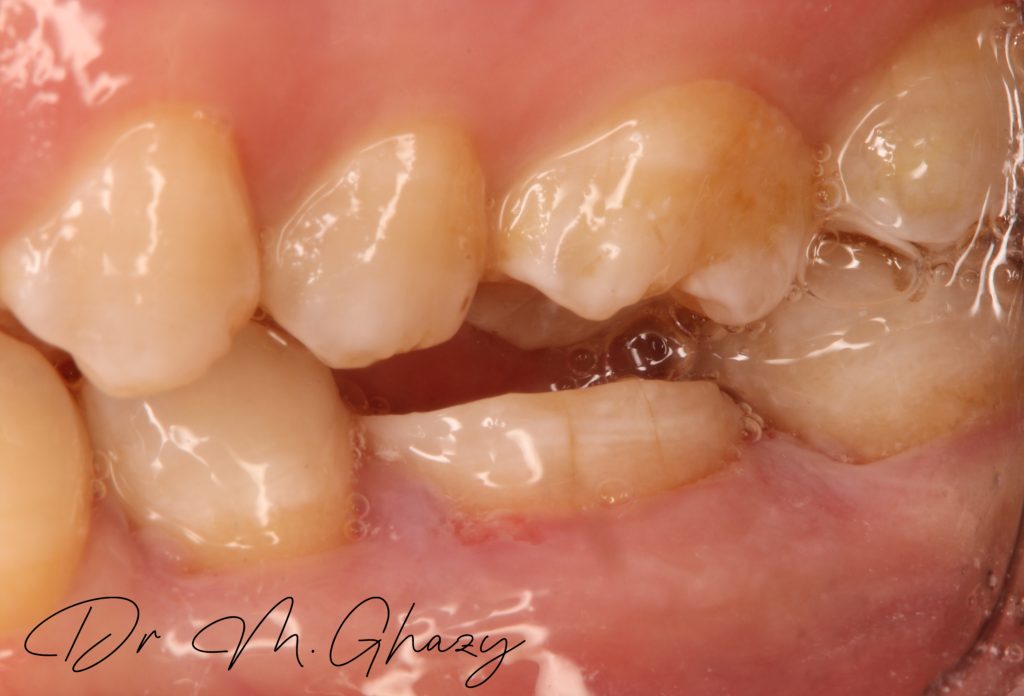

Pre-operatve bite